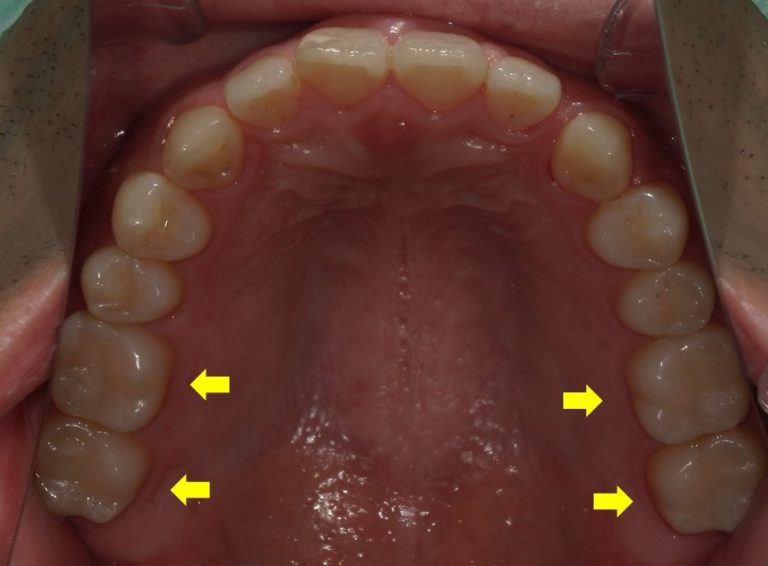

このように保険診療でも口腔内の条件によっては白く、きれいに治せるのです。

数年前やむなく入れた銀歯を今は保険で白くできるかもしれません。そう考えると少し希望がわきませんか?

もちろん、ケースによっては保険診療で白くきれいに治すには限界があり、審美性を追求する自費のセラミックを選択しなければいけないことも多いのは事実ですが、ここ日本で歯科医師をやっている以上は、なるべく保険診療で患者さんに笑顔になってもらいたいと思って日々診療しています。(なんて。ちょっとかっこつけてみました。笑)